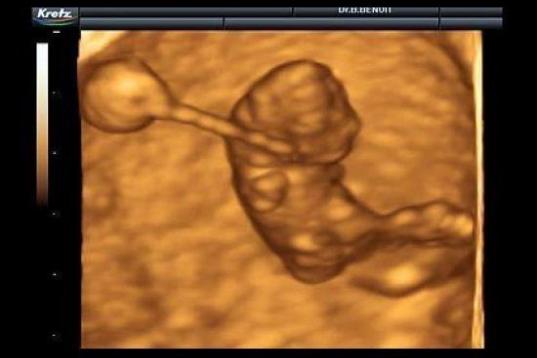

En esta galería puedes ver en fotos como es el desarrollo de un feto de semana en semana:

Desarrollo del feto, en fotos